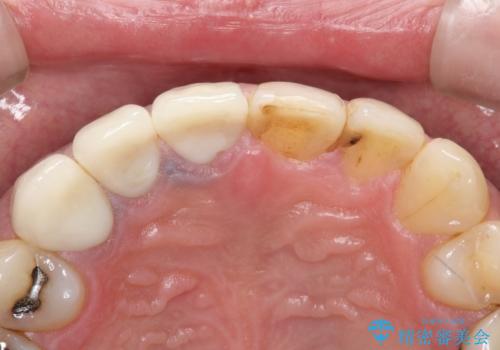

- 以前治療した上の前歯の不自然な保険のかぶせ物を自然なものにしたいとのことで来院されました。

右上の前から1番目から3番目までの歯のかぶせ物を土台から再治療することとなりました。

金属の土台を、ファイバーコアという歯根にやさしく白いものに交換して、かぶせ物をオールセラミックにしました。